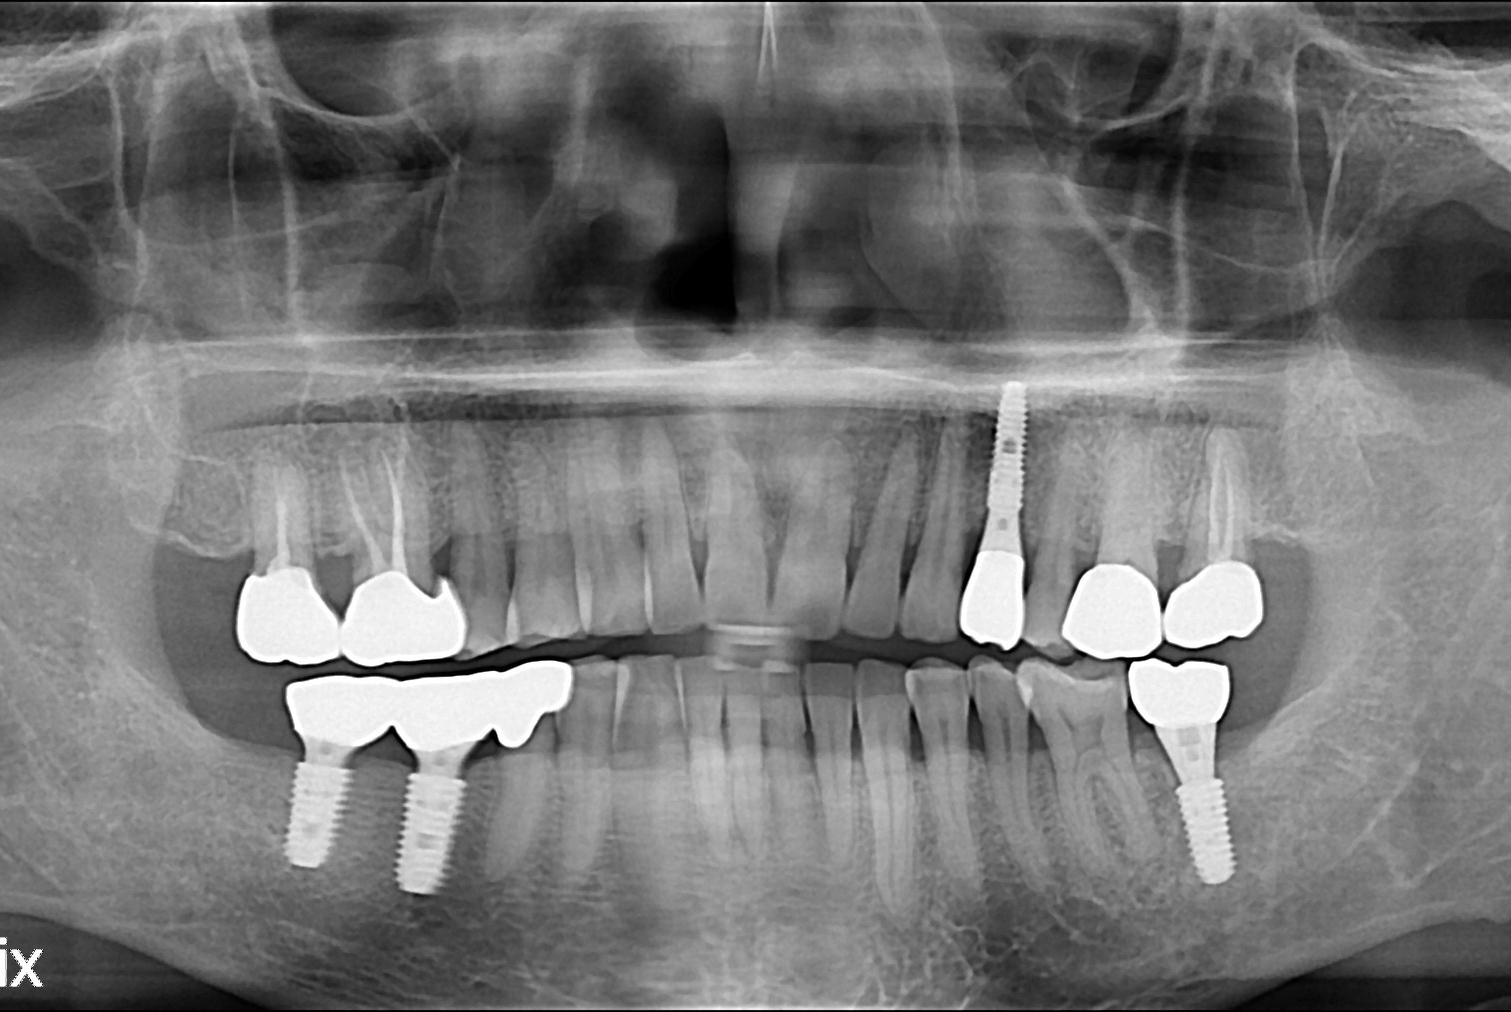

[임플란트] 임플란트

치료전 : 2019-05-10

문성호 후.jpg

치료후 : 2019-07-31

세종치과는 많은 환자와 다양한 케이스를 바탕으로 항상 편안한 임플란트 수술을 제공하고자 노력하고,

오래동안 튼튼히 쓸 수 있는 임플란트 수술을 가장 큰 목표로 삼고 있습니다